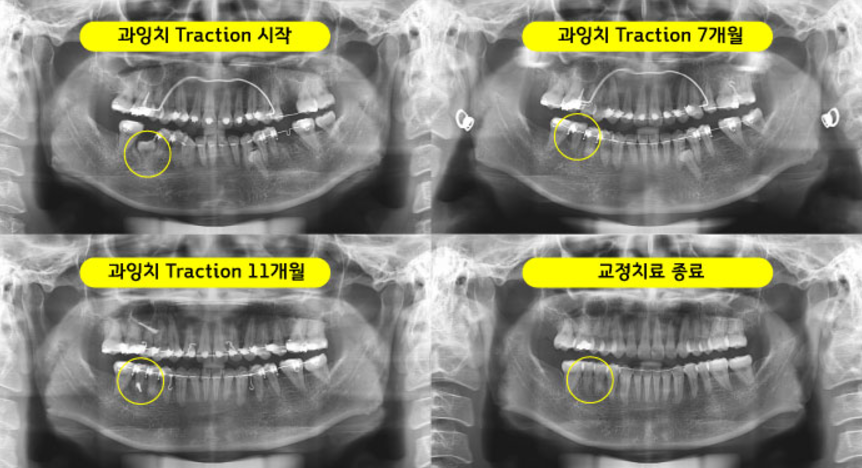

환자분의 경우 우측 과잉치로 인해 치근 흡수가 일어나 발치가 필요한 상황이었는데요. 환자분이 20대였기때문에 임플란트를 하기에는 시기가 이르지 않을까 하는 걱정이 있더라구요. 그래서 본원에서 교정치료를 통해 발치 문제를 해결해봤습니다. 사실 과잉치를 제거하려면 인접치아에 치근이 손상될 수도 있는 상황이었는데요. 치아가 전체적으로 비뚤고 입술이 나와 보이는 돌출감이 있었기에 환자분은 치아교정을 통해 이 부분도 해소하고 싶어하셨습니다.

그래서 결론은 손상된 어금니를 발치하고 사랑니를 어금니로 사용하게 하는 치아교정 플랜을 수립했는데요. LAMI 테크닉과 두 개의 와이어를 사용하는 탄댐설측교정을 진행하면서 안정적으로 치아교정을 마쳤고 결국 중심선 교합을 잘 맞추는 성공적인 교정 결과를 안아볼 수 있게 되었습니다. 환자분의 경우 매복된 과잉치를 밖으로 끌어올려 인접치의 손상 없이 안전하게 발치하여 치아교정을 마무리했는데요.

어금니를 3개를 발치하고 사랑니 및 과잉치를 사용해 임플란트 없이도 교정치료로 교합을 맞추셨답니다. 입술의 돌출감까지 해소한 까다로운 치아교정 과정이었지만 사진으로 보니 너무 만족 스럽네요. 상기 환자분의 경우 2년 후에도 안정적으로 상태를 유지해오고 있었어요. 치아교정의 경우 복잡한 과정을 거쳐야 하기 때문에 교정전문치과를 찾는 게 좋은데요. 교정치료를 해야 한다면 후회 없는 선택, 서울 가지런이치과 교정과 의원을 찾아주시기 바랍니다. 항상 친절한 상담으로 응대하고 있으니 망설이지 마세요~